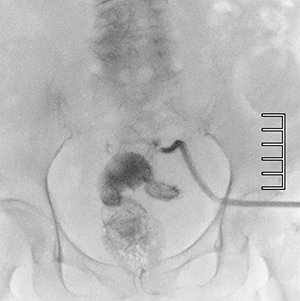

症例3 直腸穿孔に伴う膿瘍腔内のドレナージ造影

線量モードをMidにて実施。Normalに比しSN低下は顕著であるが,外径6mmのドレーンとX線不透過ライン,また造影剤の視認性は確保できている。